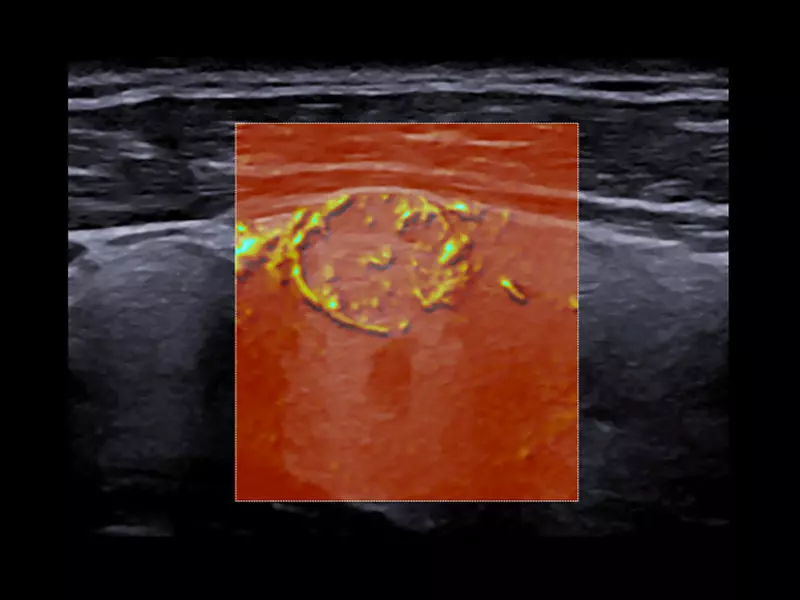

MyLab™9 Platform - Advanced hemodynamic analysis in thyroid nodule with microV

MyLab™9 Platform - Advanced hemodynamic analysis in thyroid nodule with microV

MyLab™9 Platform - High resolution imaging in testis

MyLab™9 Platform - High resolution imaging in testis

MyLab™9 Platform - XFlow in testis vascularization

MyLab™9 Platform - XFlow in testis vascularization

MyLab™E80 - microV - Thyroid

MyLab™E80 - microV - Thyroid